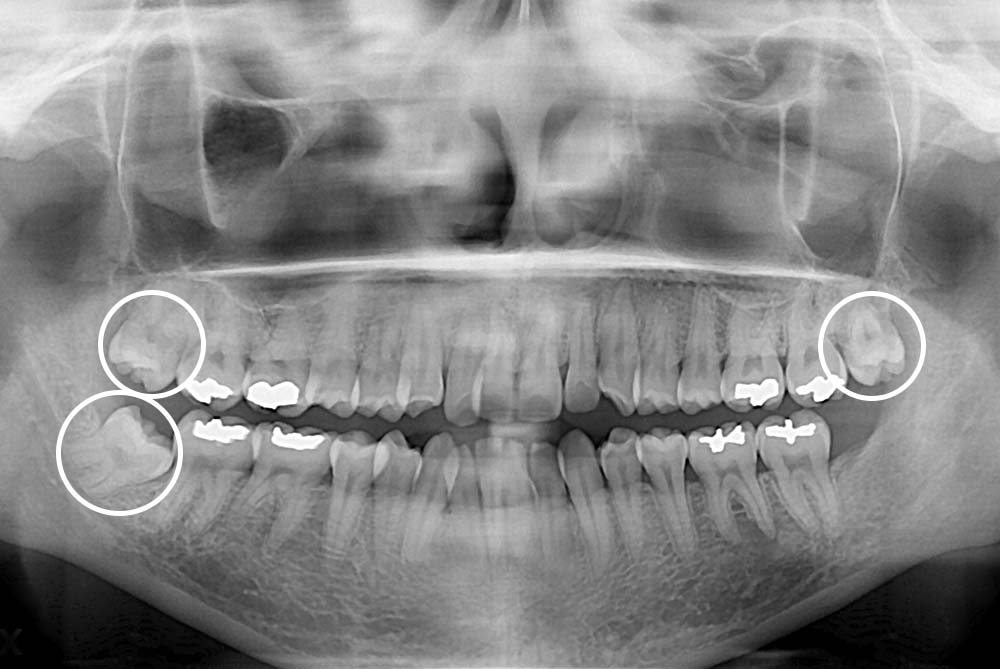

[사랑니] 매복 사랑니 발치

치료전 : 2019-06-25